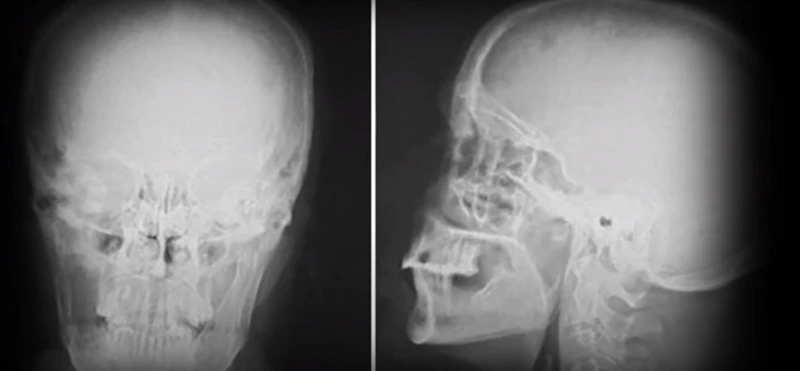

Діагноз, який чоловікові повідомили 13 лютого 2009 року, виявився невтішним: синоназальна недиференційована карцинома – рідкісна форма раку, яка вражає порожнину носа. Виживання при ній становить лише 10 відсотків.

Зазвичай при діагностуванні хвороби на ранній стадії обходяться видаленням лише самої пухлини. Але у випадку з Оуеном хвороба зайшла надто далеко. І пацієнту видалили частину носоглотки, піднебіння та праве око, а також м'язи та нерви половини обличчя.